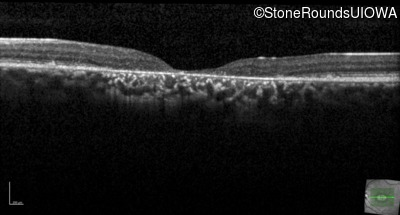

Age at visit: 29 years

This 29-year-old man had good vision until his early 20's. at which time he began to experience a slow reduction in his acuity. His driver's license was restricted at age 27.

Age at visit: 29 years (Visit 2)